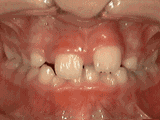

牙列拥挤,牙槽骨过窄,牙齿没有足够空间,只好前后左右高低上下乱长,经过矫正后的牙齿是这样的~